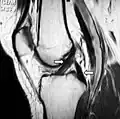

MRI shows normal signal of both cruciate ligaments (arrows)